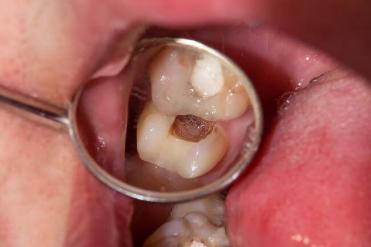

Przewlekłe włókniste zapalenie miazgi

Forma włóknista jest najczęstsza, stanowi około 69% wszystkich przypadków. Miazga przekształca się wówczas w dość gęstą, bliznowatą strukturę o szarawym kolorze, na skutek aktywnego wzrostu grubej włóknistej tkanki łącznej. Stwierdza się również ogniska zwapnień i hialinozy. W przypadku braku leczenia może dojść do zgorzeli, ropni czy mikroropni. Przewlekłe włókniste zapalenie miazgi zdjęcie